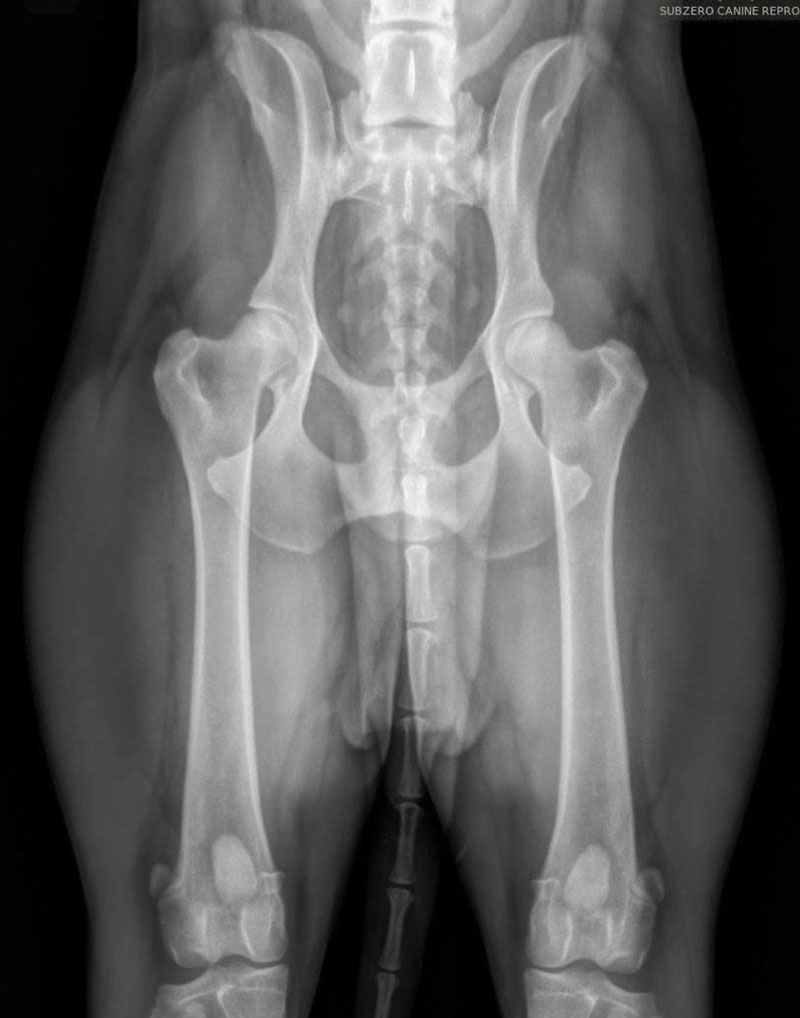

We are proud to offer state of the art Idexx radiology technology and equipment, which allows the clearest of images to be provided to our clientele. This is especially helpful when needing to determine final puppy count prior to whelp. The best time to perform a pregnancy radiograph is 55 days or later from breeding. An appointment is required for this service.

We are also proud to offer OFA (Orthopedic Foundation for Animals) image submissions. This is a requirement amongst many AKC breed clubs and may include several different image types such as:

We frequently receive inquiries regarding our success with proper positioning for OFA images, specifically for hips. Translating this success can be challenging, so we have included images of various breeds that we have taken. We take great pride in our success with these images and many others like them. As extreme perfectionists, we appreciate owners who understand that we strive for the best technique and outcome while minimizing stress and ensuring the comfort of your dog(s), particularly since all images taken here are done WITHOUT sedation.